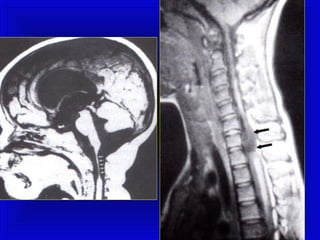

• The diagnosis is confirmed by :

Ultrasonography or MRI.

Spine and Spinal Cord

Strong traction exerted:

1. When the spine is hyperextended or

2. When the direction of pull is lateral, or

3. Forceful longitudinal traction on the trunk

while the head is still firmly engaged in

the pelvis:

(may produce fracture and

separation of the vertebrae).

• Such injuries, rarely diagnosed clinically,

are most likely to occur with shoulder

dystocia.

• The injury occurs most commonly at the

level of the 4th cervical vertebra with

cephalic presentations and

• The lower cervical-upper thoracic

vertebrae with breech presentations.